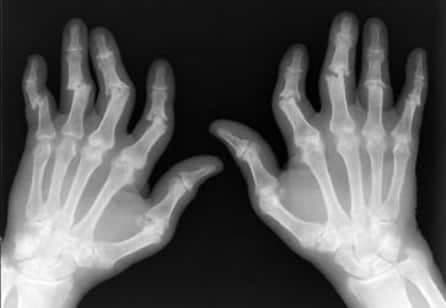

Romatoid Artrit (El)

Elde Romatoid Artrit Romatoid artrit; eklemlerin iltihabı, ellerin ve vücudun diğer bölümlerinin görüntüsünü ve fonksiyonunu etkileyebilen ve sakat...

Klinik kullanımı Romatoid Artrit (RA); birçok eklemi özellikle metakarpal ve phalengeal eklemleri etkileyen inflamatuar bir hastalıktır. Bu...